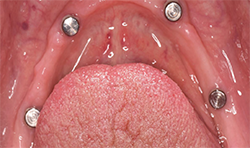

After normal healing and integration, 5 x 5 mm healing abutments with 2.5 mm wells were placed. At the impression appointment, the sulcus was prepared using a sulcus reamer and a PVS impression was taken and sent to the lab. The patient was happy with the wax try-in and the lab was instructed to finish the case. Delivery was uneventful (Figs. 5, 6).

At a second appointment, four Bicon SHORT implants, three 4 x 6 mm and one 3.5 x 8 mm were placed in the mandibular arch (Figs. 9, 10). After normal healing time, both the maxillary and mandibular arches were fitted with a fixed hybrid prosthesis fabricated from a TRINIA substructure and Ceramage denture teeth. The patient was happy with the fit, function and comfort (Fig. 11).

Using the Bicon implant system and telescoping crown abutments, the TRINIA base is a perfect match. Within the system of four implant copings, two are passive and two are retentive. The patients report the restorations feel natural, lightweight and chew and function similar to their natural dentition.